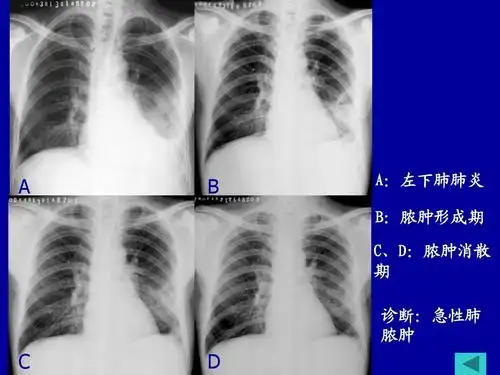

肺脓肿ppt